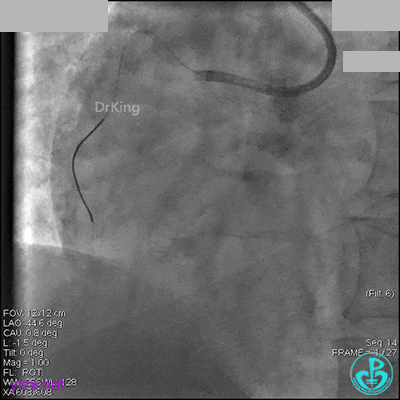

右冠脉中段充分扩张后欲植入3.5×38mm支架时,支架难以通过中远段扭曲处,且指引导管、导丝弹出飞扬。反复尝试导丝重新到达右冠脉远端时通过不顺利,局部造影剂滞留,远端血流接近3级。

右冠脉血流3级,患者无症状,终止手术。

术后患者无特殊不适。